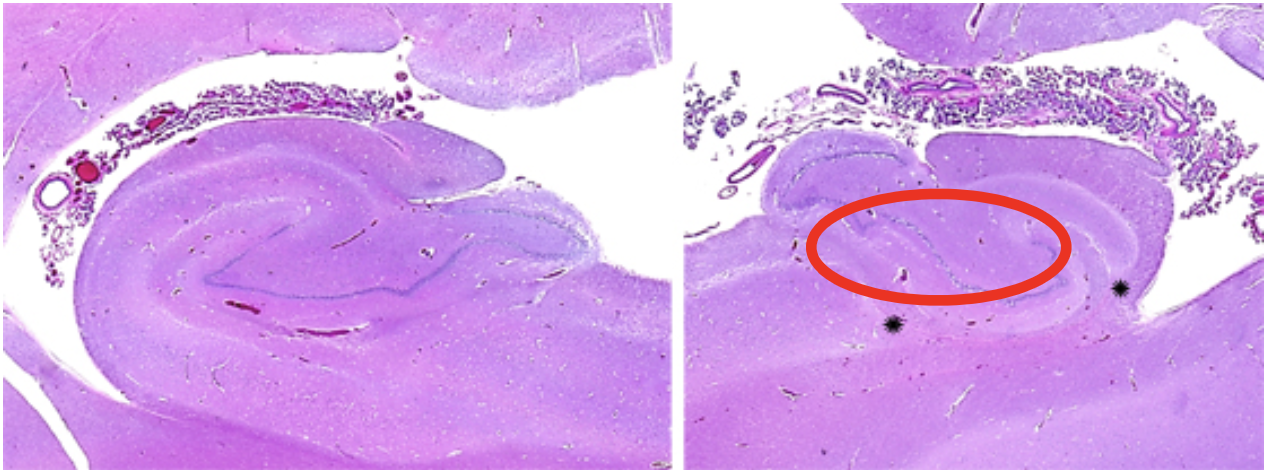

Transient global hypoperfusion - acute histopathology

Acute ischemia of the Purkinje cells. (circle)

Chronically, there is loss of neurons and proliferation of the surviving astrocytes (gliosis).

– In the cerebellum, this is called Bergmann gliosis. (arrow)

Transient global hypoperfusion - chronic histopathology

Chronically, there is loss of neurons (circle and (arrow)

Chronically, there is proliferation of the surviving astrocytes (gliosis).